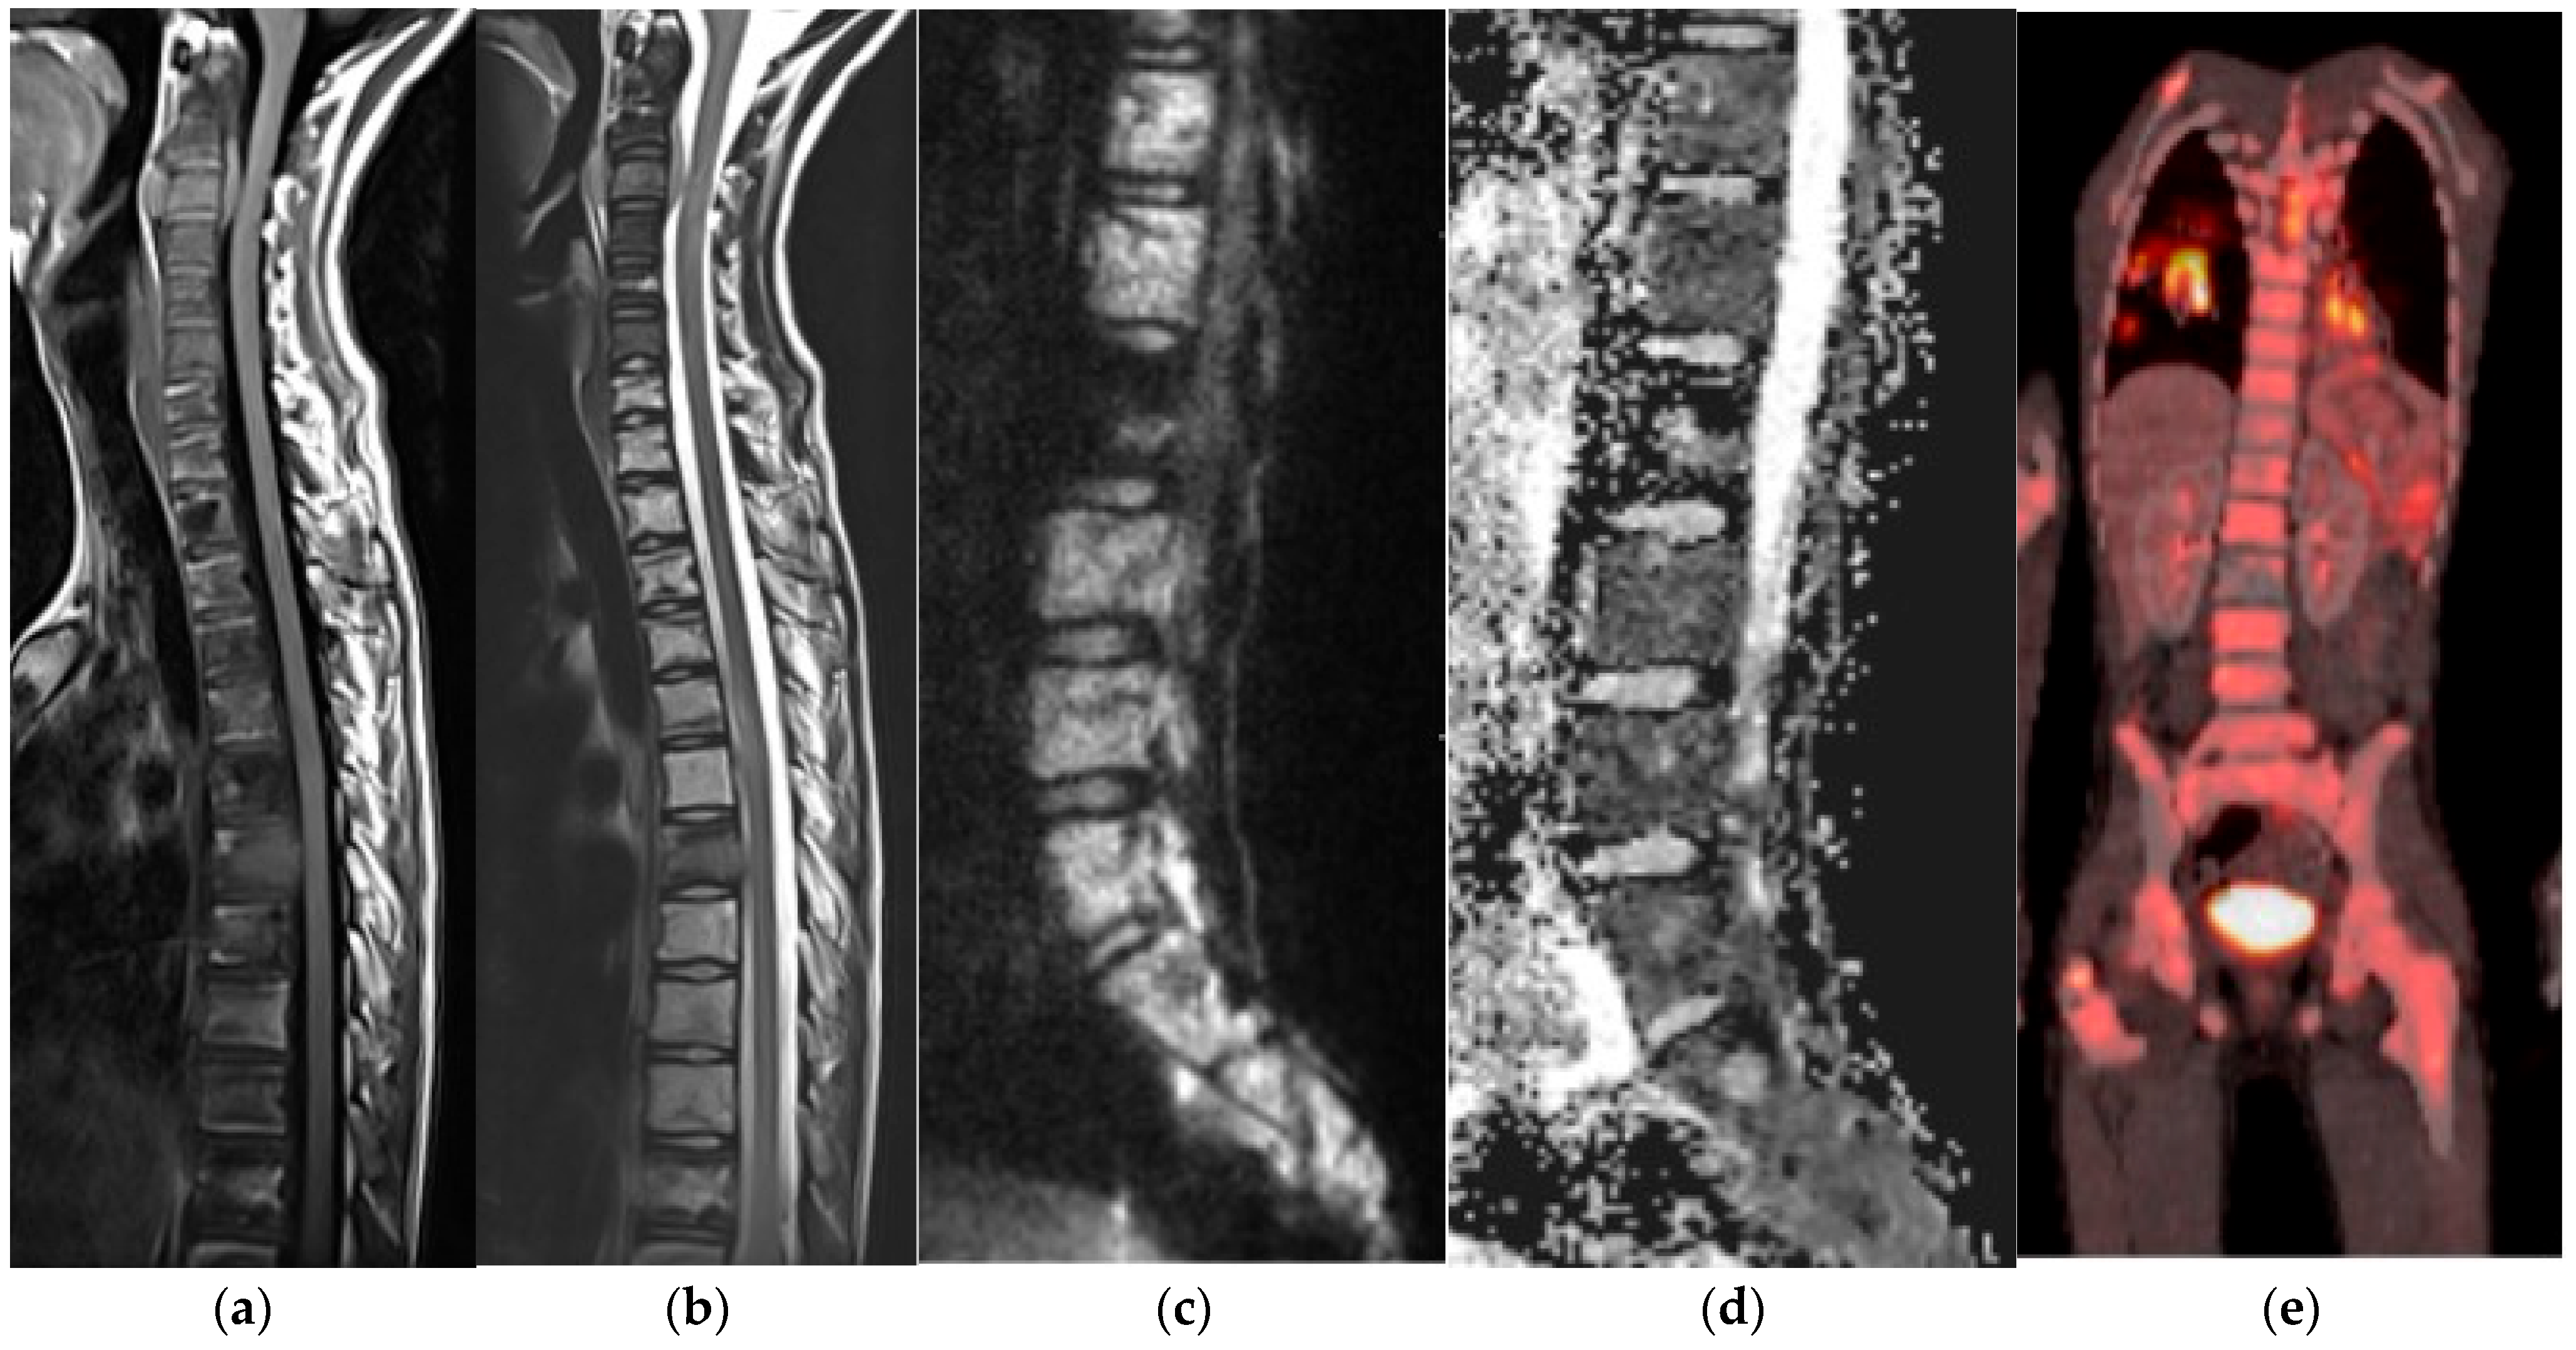

2.10. Primitive Small Round Cell

Ewing Sarcoma

Langerhans Cell Histiocytosis